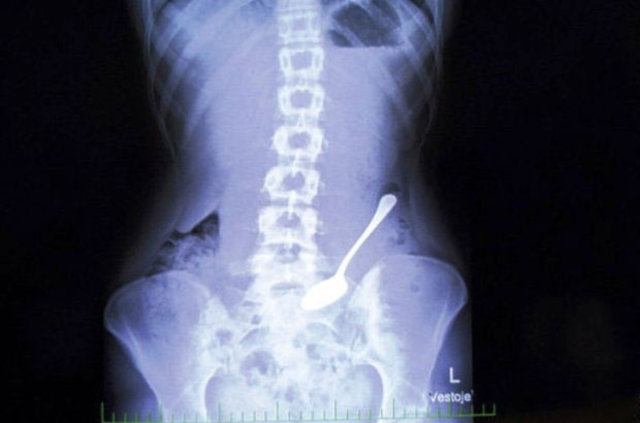

Cumhuriyet Üniversitesi (CÜ) Tıp Fakültesi Araştırma ve Uygulama Hastanesi Göğüs Cerrahisi Anabilim Dalı Servisi'nde insanların yanlışlıkla yuttuğu cisimlerden oluşturulan koleksiyon, görenleri hayrete düşürüyor.

Operasyonla mideden ya da nefes borusundan çıkan parçalar zaman zaman hekimleri bile şaşırtıyor.

Aralarında iğne, metal kolye, vida, protez diş, dikiş iğnesi, kemik parçası, pisi pisi otu, çivi ve akasya dikeni de bulunan cisimleri koleksiyon yapan hekimler, vatandaşların ağızlarına aldıkları şeylere dikkat etmeleri gerektiğini dile getiriyor.

Prof. Dr. Ekber Şahin, AA muhabirine yaptığı açıklamada, Sivas'ta son yıllarda yetişkinler ve çocukların yuttuğu yaklaşık 700 civarında yabancı cismi insanların mideleri ve nefes borularından başarıyla çıkardıklarını söyledi.

Operasyonlarda yabancı cisimlerle karşılaştıklarını ve şaşırdıklarını anlatan Şahin, "Çıkardığımız bu cisimlerin bir kısmıyla koleksiyon oluşturduk. Yıllardır çıkardıklarımız biriktirdiklerimizin 20-30 katı kadar" dedi.

Çıkardıkları cisimler arasında iğneler, metal kolyeler, vidalar, protez dişler, dikiş iğneleri, kemik parçaları, pisi pisi otları, çiviler ve akasya dikeni bulunduğunu kaydeden Şahin, "Bir insan akasya dikenini nasıl yutabilir diye çok şaşırıyoruz.